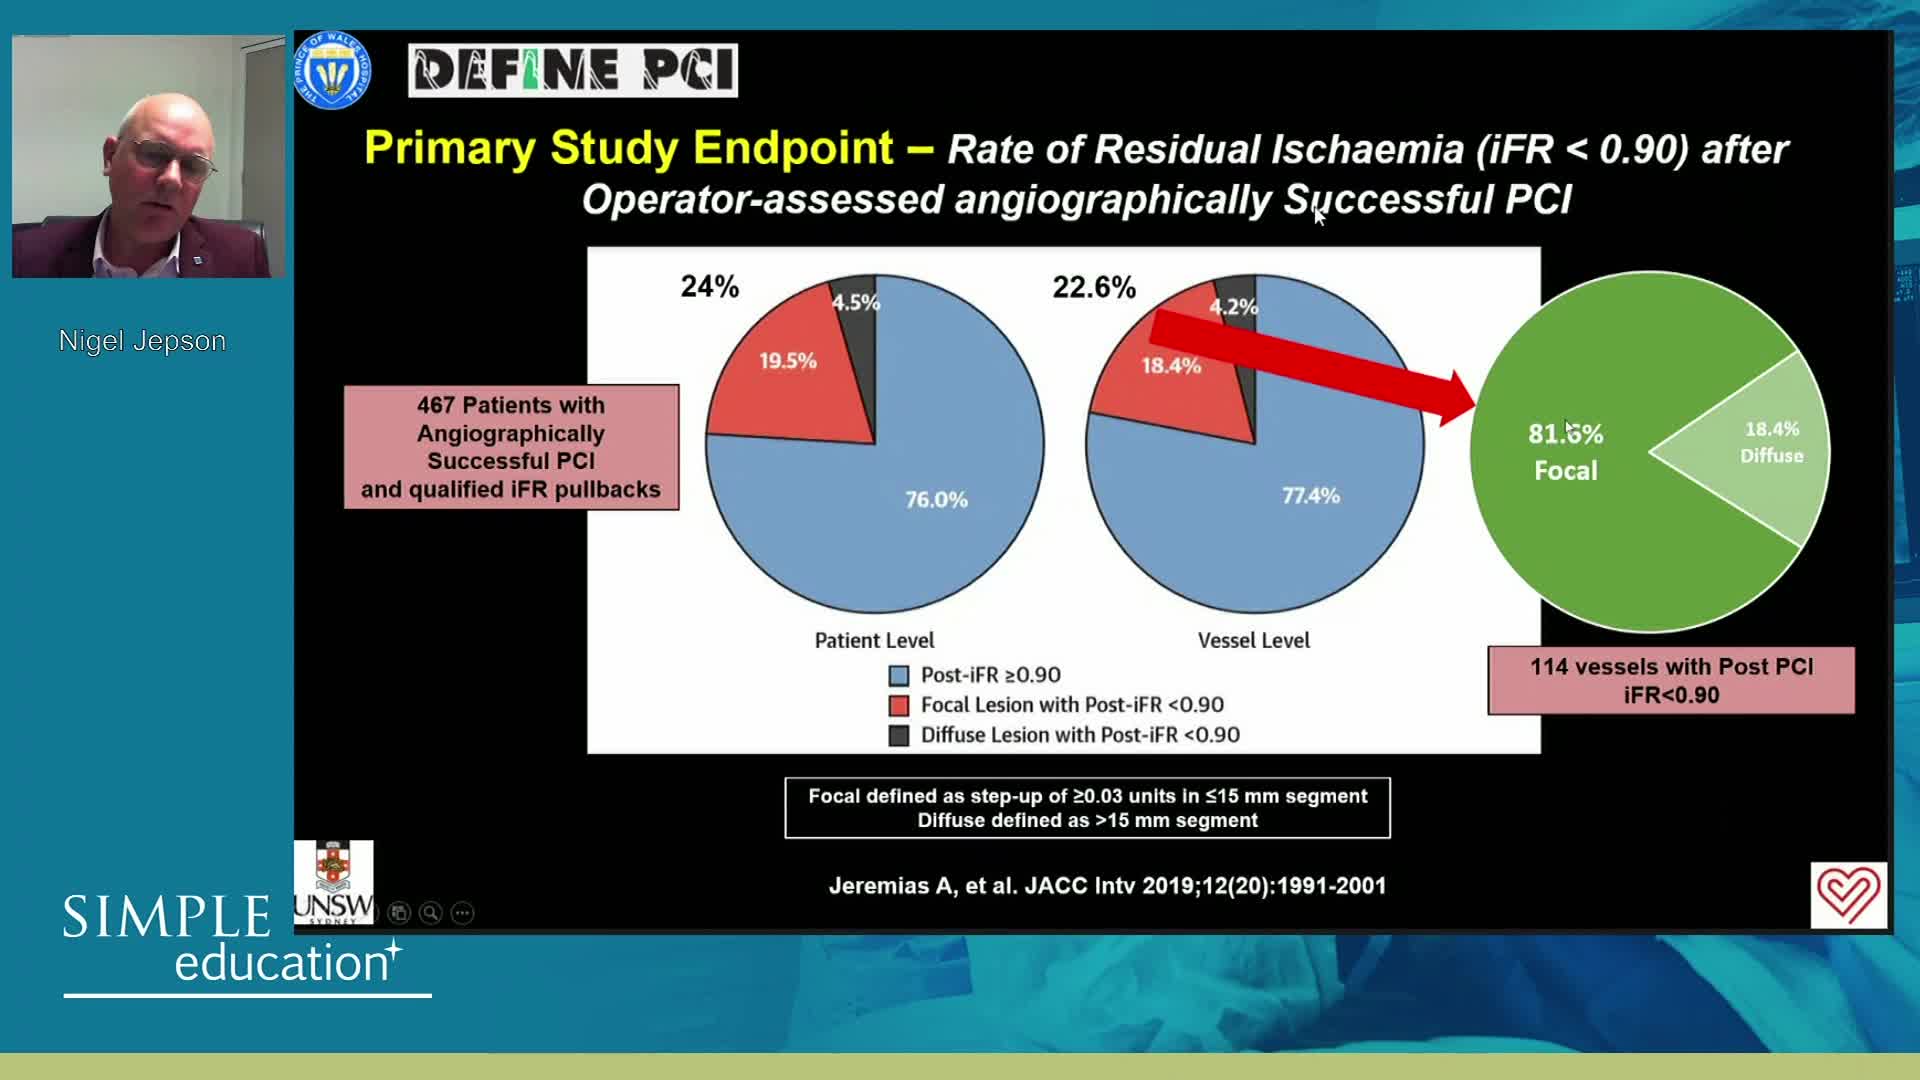

DEFINE-GPS Leading to Full Integration of Coronary Physiology to PCI Decision-Making

DEFINE-GPS leading to full integration of coronary physiology to PCI decision-making

Coronary physiology gate keeper or guide to coronary PCI? Rationale and design of DEFINE-GPS

Using SyncVision Co-registration to distinguish between focal and diffuse coronary disease. - Prof Giuseppe Tarantini

Essential steps for physiology-based PCI planning and guidance - Dr Allen Jeremias